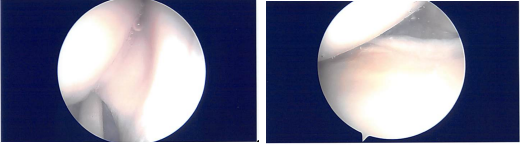

Examination of the medial meniscus showed a tear of the anterior horn of the medial meniscus which was clean. The intercondylar notch showed an intact ACL. Lateral tibiofemoral compartment examination was normal.

After thorough Irrigation, final pictures were saved and the wound was closed. Then, 40 mg of Depo-Medrol was injected in the left knee after the surgery.